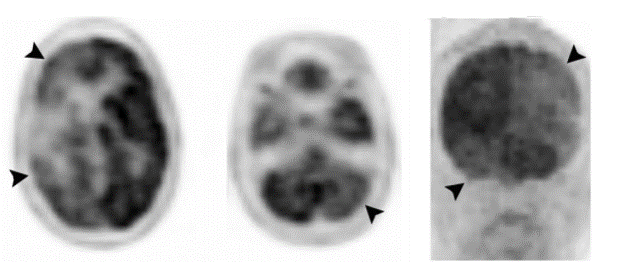

Alzheimer disease

corticobasal degeneration

frontotemporal dementia

lewy body dementia